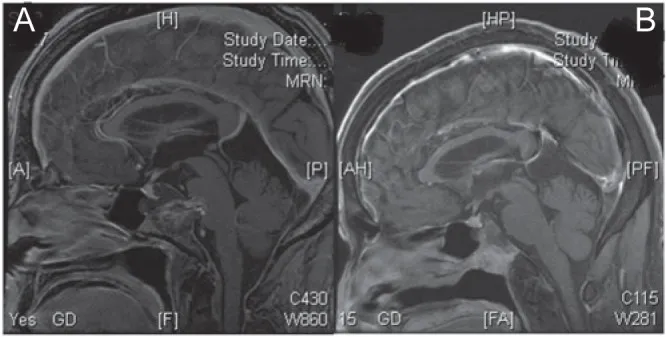

A.术前矢状位钆增强磁共振成像显示斜坡脊索瘤伴小型硬膜下肿块侵犯脑桥。

B.通过经口-经腭入路成功切除硬膜下肿瘤。术中对直径7毫米的硬膜缺损进行了处理,在保留蛛网膜层的前提下未发生脑脊液漏。硬膜缺损采用涂抹纤维蛋白胶的腹部脂肪进行封闭,患者术后未出现脑脊液漏。